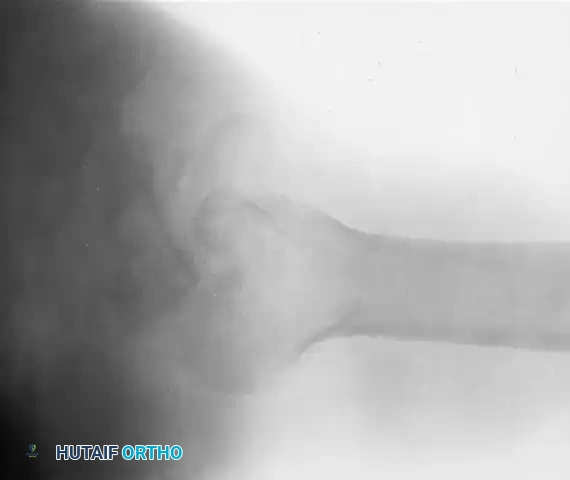

Clinical Pearl: Posterior dislocations are notoriously missed on initial presentation. As demonstrated in the radiographs above, an anteroposterior (AP) radiograph may show only subtle changes, such as the "lightbulb sign" or loss of the normal elliptical overlap of the humeral head and glenoid. An axillary lateral radiograph is absolutely mandatory to confirm the posterior displacement of the humeral head and to quantify the extent of the anterior impression defect where the posterior glenoid rim is incarcerated.